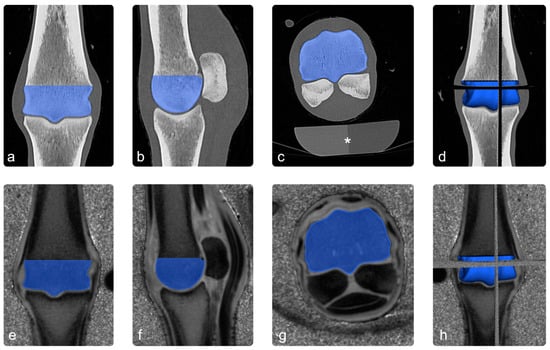

Co-registered images were loaded into an open-source 3D imaging software (Slicer Version 5.4.0 [46]), and the diaphyseal part of the segmentation of the third metacarpal/metatarsal bone was manually removed to match the ROI to the distal condyle of the third metacarpal/metatarsal bone (see Figure 2).

Figure 2.

Image processing: images (a–c) show the ROI (blue) in the coronal, sagittal, and transverse sections of the CT scan. In image (d), the three planes were combined to a 3D-ROI. Images (e–h) show the co-registered PI images in the same way. The asterisk in image (c) highlights a standard osteodensitometry phantom containing calcium hydroxyapatite and demineralized water, which was used to calculate bone-mineral density.